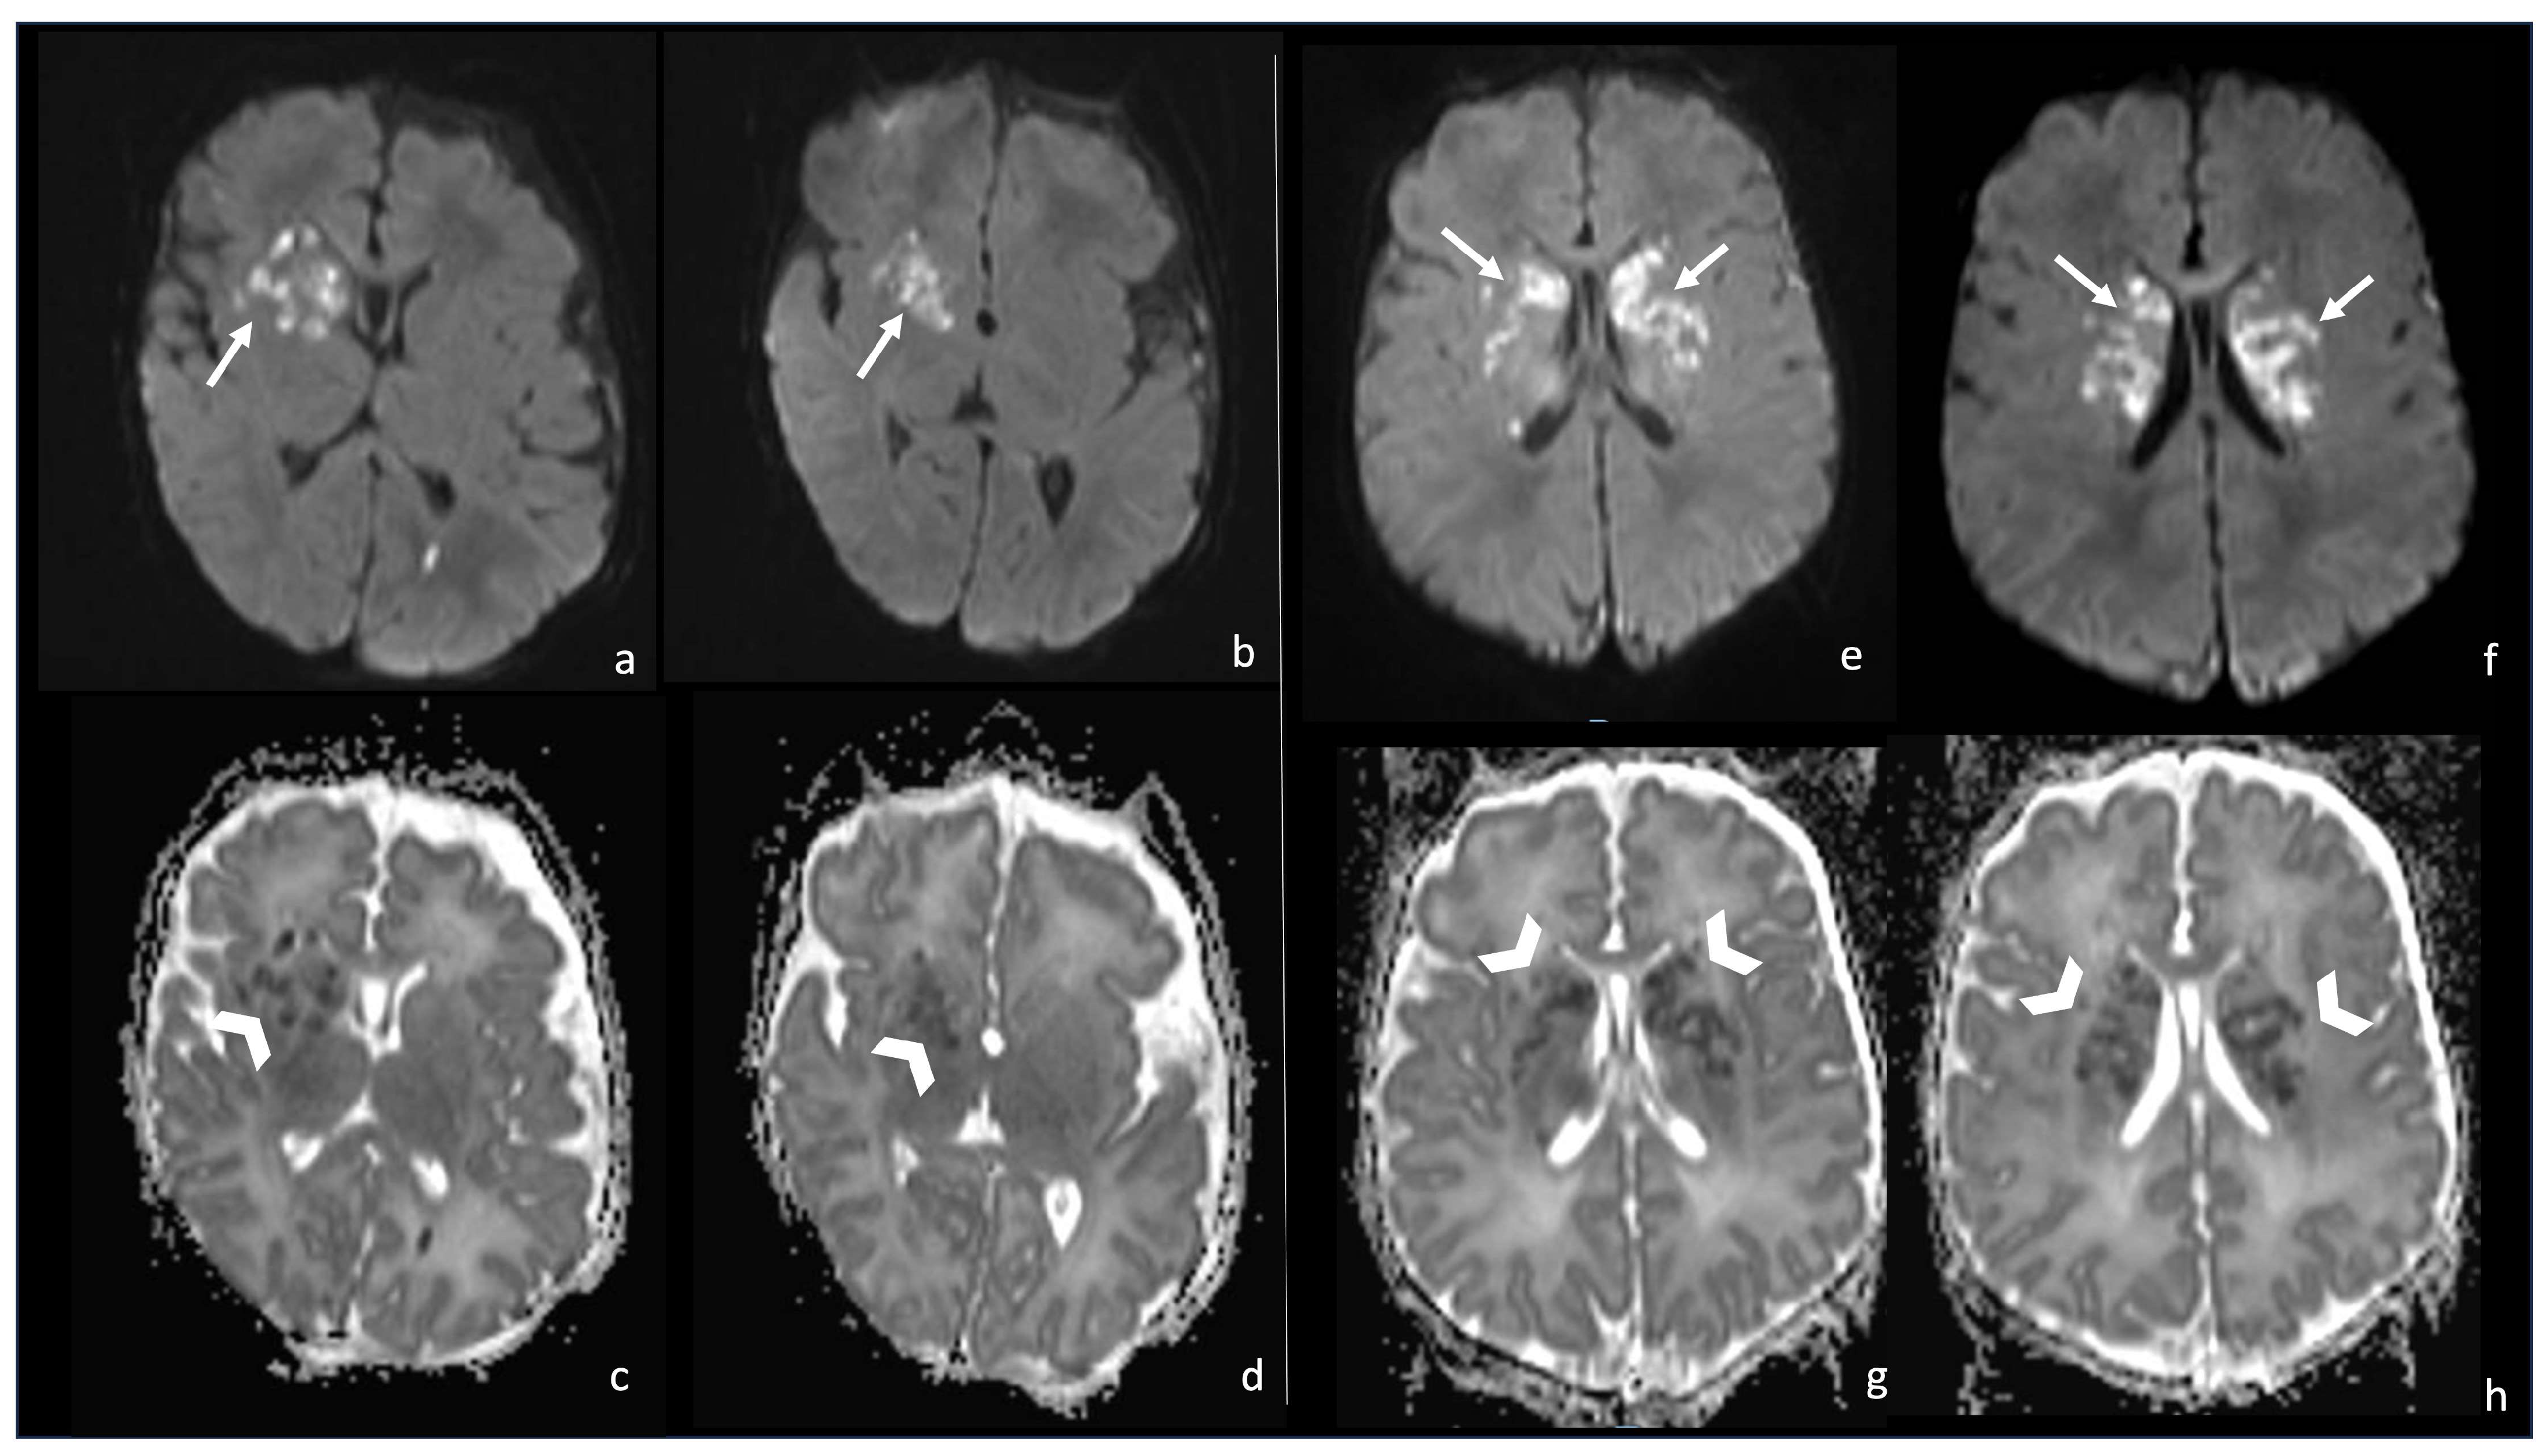

Figure 9.

Two cases of newborns, namely a 1-month-old girl and (e–h) a 2-month-old girl, affected by Group B Streptoccoccus meningoencephalitis (a–d). In both cases, there are multiple punctate ischemic lesions with a massive brain involvement characterized by diffusion restriction on axial DWI sequences (arrows in (a,b,e,f)) and low ADC values (arrowheads in (c,d,g,h)).

At MRI examination, the pattern of multiple or diffuse infarcts is typical of Streptococcal Meningitis and is rarely seen in meningitis secondary to other microorganisms. Infarcts are often bilateral and basal ganglia involvement is predominant (Figure 9). In literature, authors speculate that small-vessel vasculitis or inflammatory encephalitis may be responsible for these findings [51,52,53,54,55].